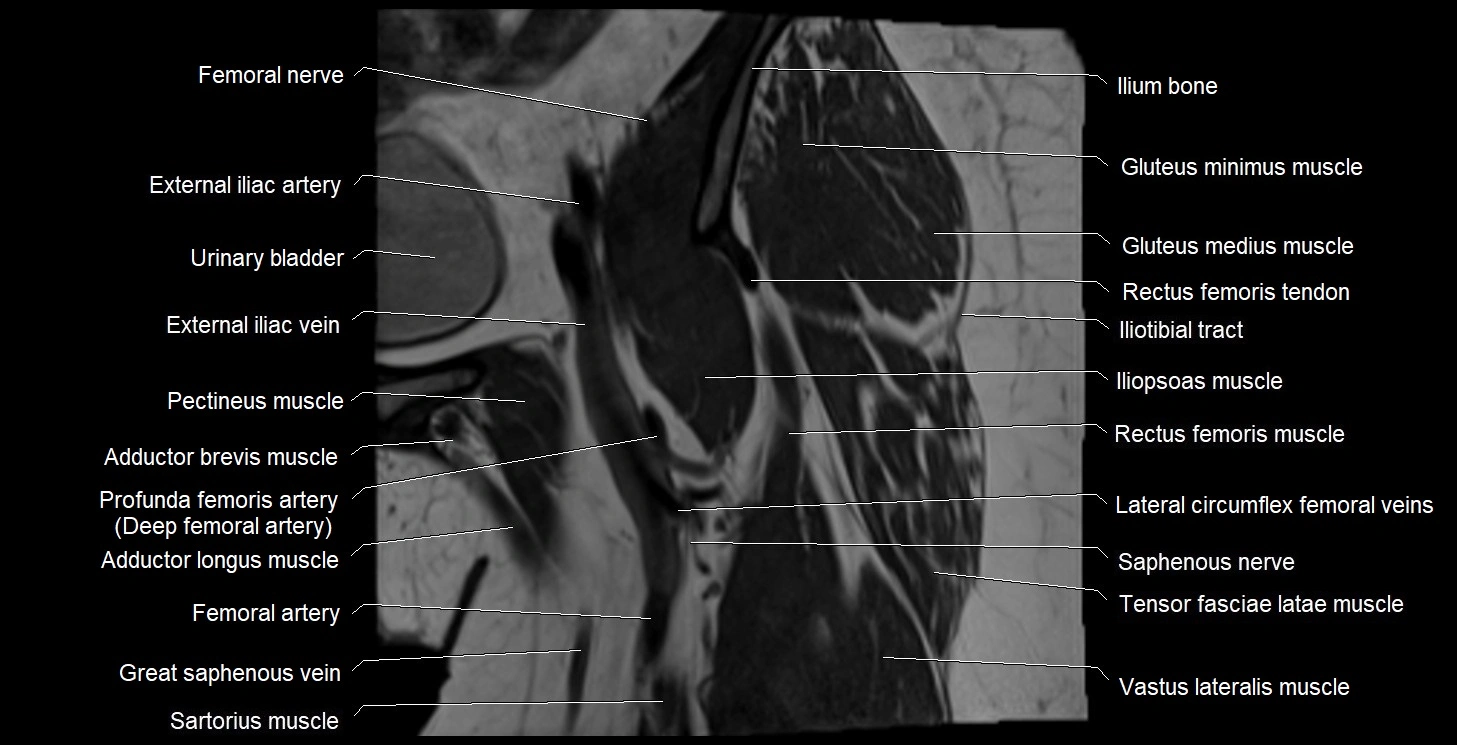

- Femoral nerve

- External iliac artery

- External iliac vein

- Urinary bladder

- Iliopsoas muscle

- Iliotibial tract

- Pectineus muscle

- Femoral artery

- Saphenous nerve

- Sartorius muscle

- Vastus lateralis muscle

- Gluteus minimus muscle

- Gluteus medius muscle

- Ilium bone

- Lateral circumflex femoral veins

- Rectus femoris muscle

- Tensor fasciae latae muscle

- Vastus intermedius muscle

- Deep femoral artery (profunda femoris)